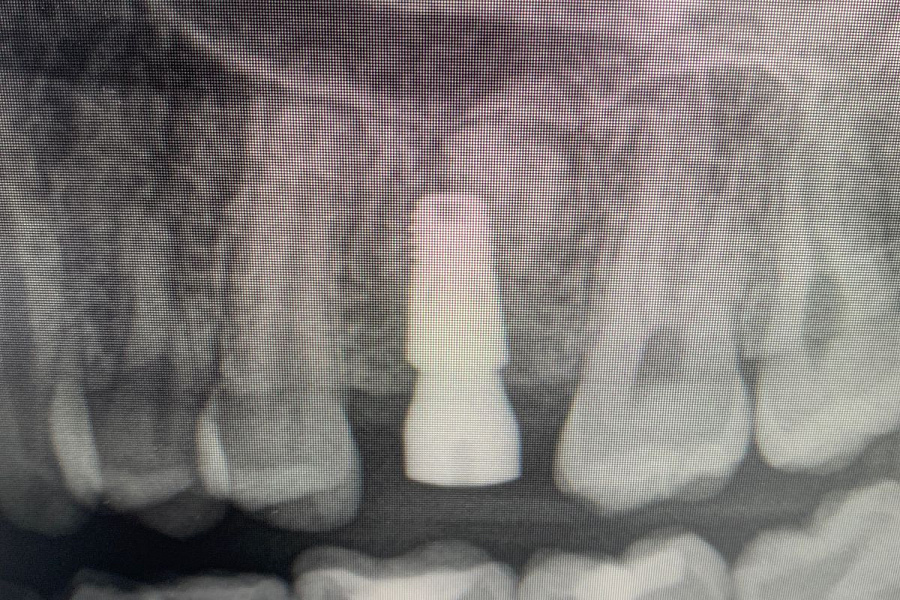

Через 6 месяцев после подсадки кости - контрольный снимок и установка зубного имплантата.

Спустя 6 месяцев пациент готов к протезированию.